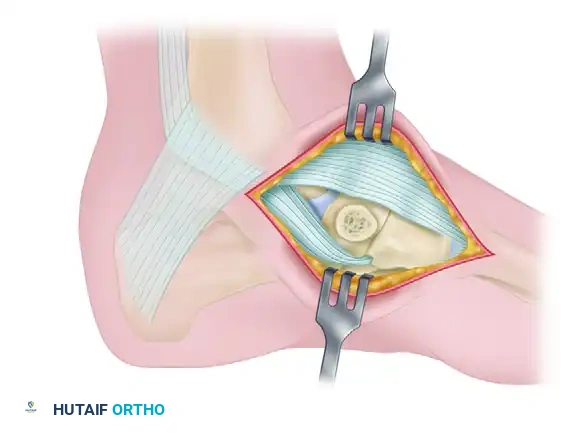

Step 4: Medial Column Flush Resection

Once the accessory fragment is removed, the remaining medial tuberosity of the primary navicular often remains excessively prominent. Use an osteotome or oscillating saw to resect the medial prominence of the navicular so that it is perfectly flush with the adjacent medial cuneiform and the head of the talus. This prevents postoperative shoe-wear irritation.

Figure 82-39D: Accessory navicular removed and the tuberosity of the navicular cut flush with the adjacent cuneiform and talus.

Figure 82-39 (Continued): Final anatomical alignment demonstrating the flush medial column.